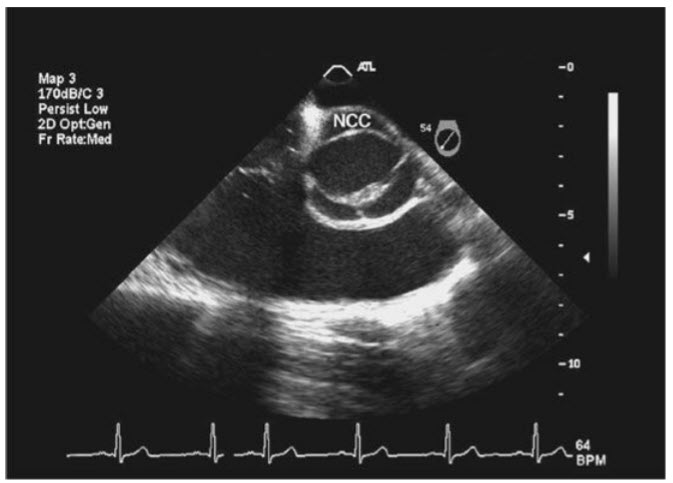

The finding in the transthoracic images in Figures below A and B

A. Apical four-chamber view (TTE). B. Apical four-chamber view with color Doppler.

is commonly associated with which of the following lesions?

Cleft MV. The image displays an apical four-chamber view of a patient with a primum ASD. (Note Fig. B in question with color Doppler shows left-toright shunting through the ASD.) This is part of either a partial or complete AV canal defect. A complete AV canal defect includes a primum ASD, a cleft anterior mitral leaflet, and a widened anteroseptal tricuspid commissure. A partial AV canal defect is as above but without the VSD. Note that because of the long-term, significant right-to-left shunt through the ASD in this patient the right side is dilated and there is right ventricular hypertrophy from pulmonary hypertension. The short-axis view of the MV (Fig. A below) demonstrates the cleft anterior mitral leaflet, which “splits” in the center, as opposed to opening like a fish mouth as is seen with normal MVs. Figure B below is a drawing showing normal short axis of MV versus cleft MV.

A. Parasternal short-axis view of the mitral valve (TTE). B. Drawing comparing the parasternal short-axis view of a normal mitral valve to the opening of a cleft anterior mitral leaflet.